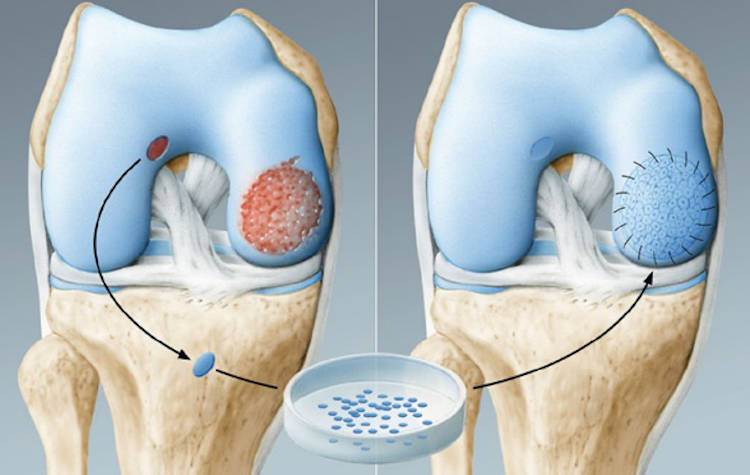

Τεχνική μεταμόσχευσης αυτόλογων χονδροκυττάρων. Γίνεται σε δύο στάδια, θα χρειαστούν δηλαδή δύο χειρουργεία, όπου στο πρώτο χειρουργείο αρθροσκοπικά λαμβάνονται τεμάχια χόνδρου και αποστέλονται σε ειδικά κέντρα για πολλαπλασιασμό των χονδροκυττάρων.

Στο δεύτερο χειρουργείο τα αναπλασμένα χονδροκύτταρα μεταφέρονται σε ειδική μεμβράνη και τοποθετούνται στη βλάβη.